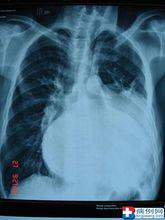

雙肺肺炎

胸片右圖可見雙肺斑片狀陰影

陰影模糊不清

雙肺呈毛玻璃狀